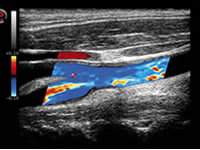

Hacemos tratamiento de varices mediante escleroterapia por microespuma. Realización de Dúplex Venoso y procedimientos guiados por ecografía.